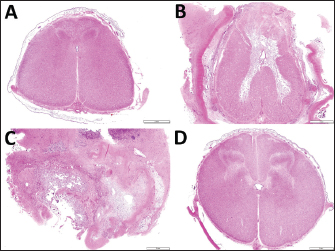

Histopathological examination revealed a loss of their normal histological structure at the locations of the L1 and L2 (Fig. 5). The histopathological abnormalities included extensive necrosis (malacia) in the gray matter, diffuse white matter degeneration with axonal swelling (spheroids), and gliosis and scarring of the dorsal part of the spinal cord, including the dorsal funiculus (Fig. 4C, D). The dura mater was thickened diffusely due to fibrous scar tissue formation. Based on clinical and histopathological examination results, the destructive changes of the gray matter accompanied by neuron loss were considered to contribute to the irreversible development of hindlimb paralysis. The degenerative changes within the white matter might also be a secondary change.

Fig. 5. Transverse section images of the spinal cords at the locations of the thirteenth thoracic vertebra (A) and the first, second and fourth lumbar vertebras (B, C and D, respectively). (A) Degeneration of the white matter is seen diffusely in the dorsal funiculus and sporadically in the ventral funiculus and the lateral funiculus. (B) Extensive malacia is seen within the gray matter. (C) The spinal cord’s structure is destroyed due to extensive malacia with fibrous scar formation. (D) Degeneration of the white matter is mild. Bar, 2 mm.